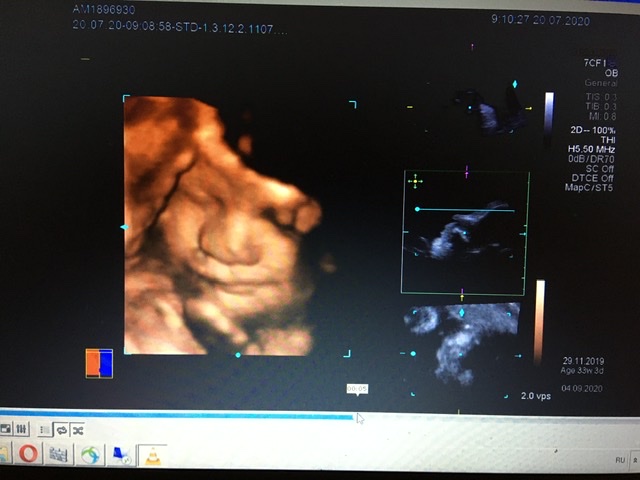

Все будет видно) но мне узист советовал в 28) там уже прям человек))мы почти в 27 делали если считать по 1 скринингу. Очень долго пытались выловить лицо,сынуля каждое узи показывает писюн)))личико прячет. Мы не пожалели,что сходили 😍нам понравилось. Он там зевал,показывал язык )))ну и складывал на лицо все,что можно..ручки,ножки,пуповину)))

вот в 34 ещё делали)) Обычно все детки поджимают нижнюю губу,наш наоборот,выпячивает 😀ой,я так рада была,когда увидела его губы))) у мужа пухлые,красивые,как раз хотела,чтобы как у мужа были))